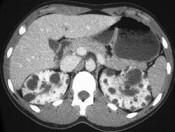

问题 男性,40岁,因腰痛血尿就诊,B超检查发现肾脏增大,CT表现如图所示,追问病史发现家族中有类似疾病,最可能考虑为 ( )

选项 A.多囊肾 B.肾积水 C.多发性肾囊肿 D.肾肿瘤 E.肾结核

答案 A